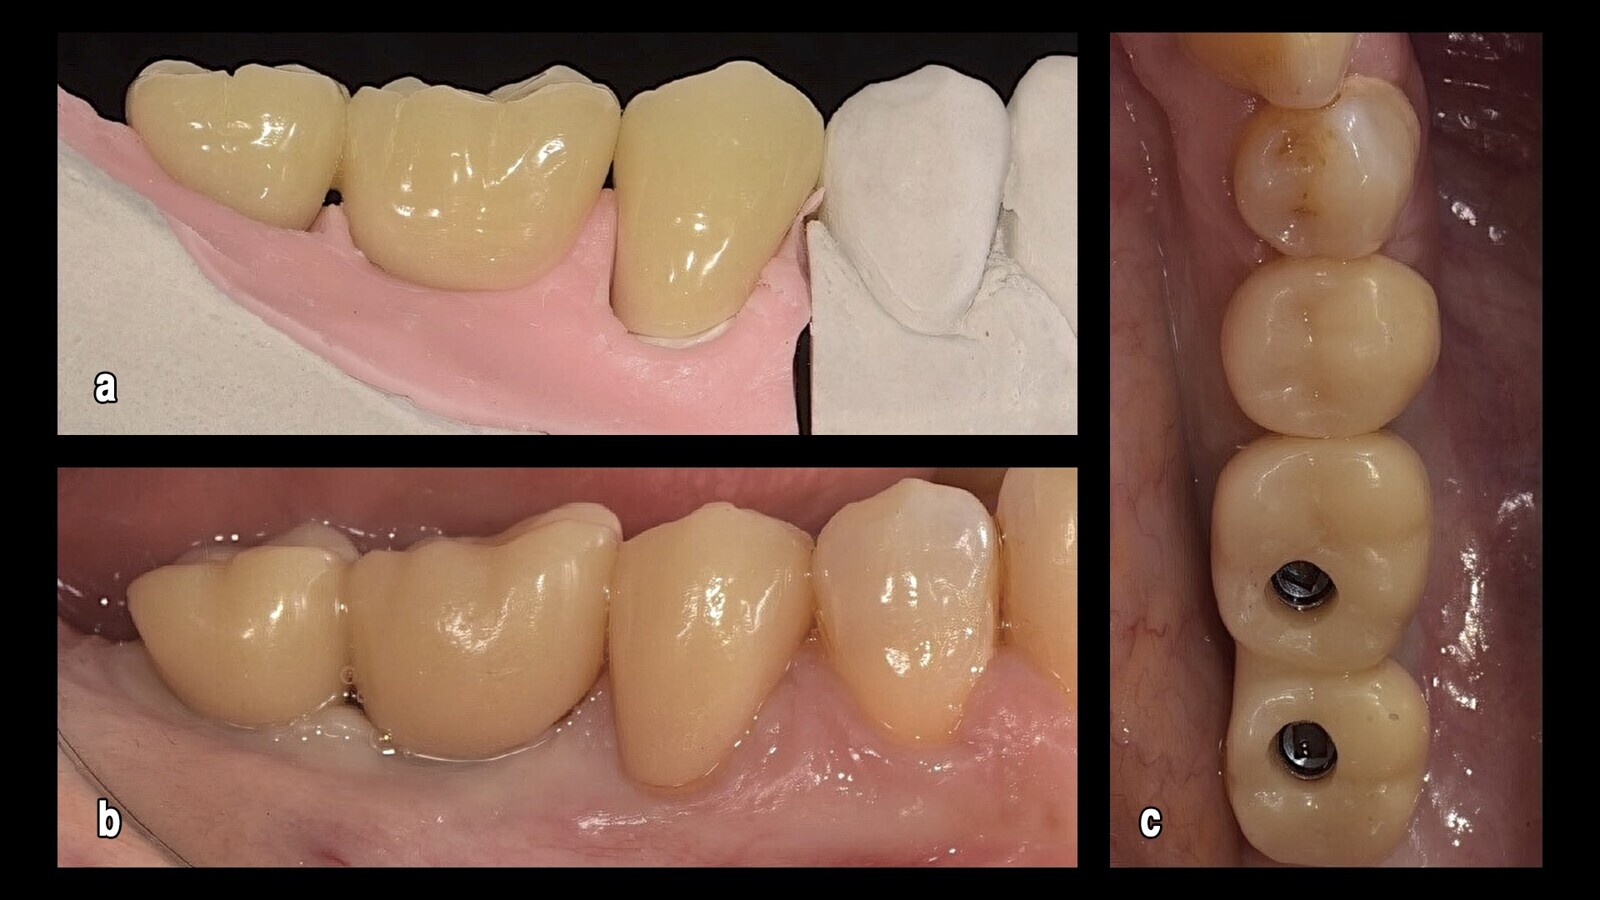

Figura 19. Las coronas de resina fueron entregadas tanto para los implantes (a) como para el elemento natural preparado (b). En un caso de reconstrucción (es decir, con implantes ahora completamente osteointegrados) (c), la elección de entregar un provisional, antes del definitivo, se hizo con el objetivo de permitir una rápida restauración de la masticación y el acondicionamiento del tejido para asegurar la reforma de las papilas interdentales.

Figura 25. Este prototipo de aluminio (a, b, c), se probó en boca.

Figuras 31. La prueba en boca se realizó después de la estratificación de la cerámica cruda.

Figura 32. Así, nos saltamos el paso de la prueba de circonio debido a la precisión de las coronas de aluminio, como se observa desde distintos ángulos.

Figura 35. En esta imagen, que precede al atornillado de 4.6, 4.7 y al cementado de 4.5, se puede apreciar el acondicionamiento de los tejidos y el aspecto natural de las parábolas.

Figura 36. Esto permite el camuflaje del artefacto también gracias a las reducidas dimensiones del implante que, en la rehabilitación fija (a), permanece dentro del túnel mucoso (b).